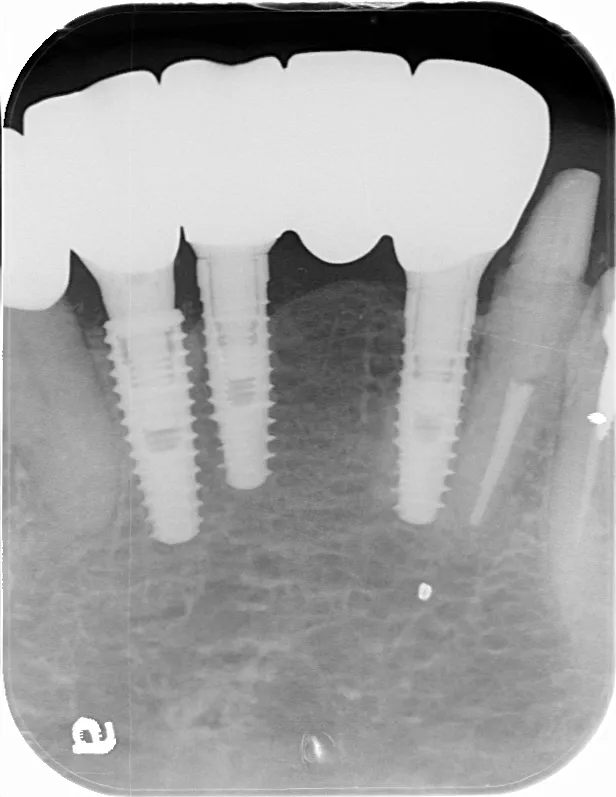

ボーンアンカードブリッジの下顎症例です。同じようにインプラント6本で上部構造を支えることができます。

左下67 欠損に対してインプラント治療を行った症例

部分床義歯を使用していたが、どうしても慣れない上にしっかり噛むことができないためインプラント治療を希望